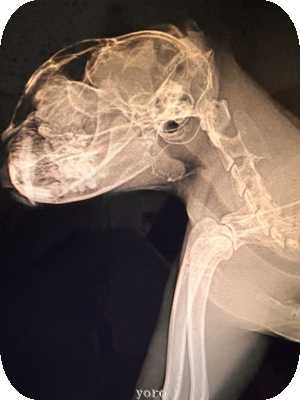

先に喉元のレントゲンアゲイン きなこ猫

のどの通りは随分とすっきりと見えるようになった

※ステロイドと抗生物質が効いて炎症が良くなってる

が

喉内部の肉芽腫かガンか?の形成物はあまり変化がない模様と

※わたしの肉眼ではよくわからなかったが

二週間後に又レントゲン予定。